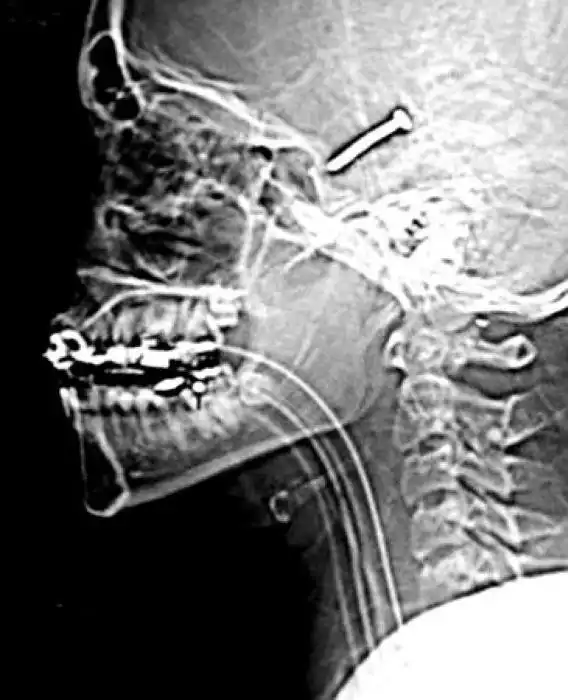

Необычные предметы в теле людей на рентгеновских снимках

На рентгеновских снимках людей порой можно обнаружить самые необычные предметы, которые находятся в их теле.